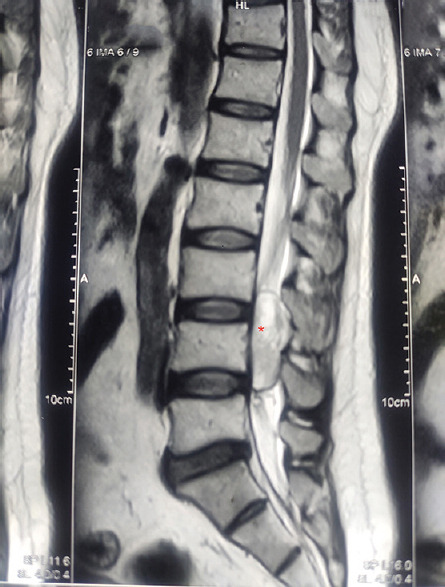

Carcinoid tumors (CTs) are slow-growing neuroendocrine neoplasms that may arise in any part of the body. They usually affect the lungs or gut. Primary intradural extramedullary CTs of the central nervous system are rare; few cases have been reported. This case report describes a 36-year-old patient with lower back discomfort, weakness, and lower leg pain for 8 months. Contrast-enhanced magnetic resonance imaging of the lumbosacral spine, from the lower L3 vertebral level to the L4-5 disc level, revealed a 4.5 cm × 2.5 cm × 1.5 cm intradural mass lesion. The main differential diagnoses were on clinical and radiographic examination: nerve sheath tumors, meningiomas, and myxopapillary ependymomas. The tumor was excised en bloc after an L3-L5 lumbar laminectomy. Histomorphology and immunohistochemistry made a definitive diagnosis of CT of the lumbar spine. Two years after surgery, there was no clinical or radiological evidence of tumor recurrence or metastasis. The present case study is intended to effectively diagnose and treat spinal intradural extramedullary CTs.